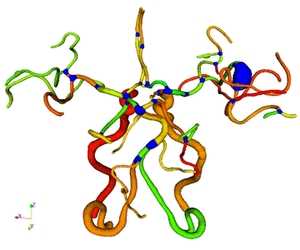

Branches of tubular structures (vasculature, trachea, neuron, etc.) in medical images are critical for the topology of these structures. In many applications, It is very helpful to be able to decompose tubular structures and identify every individual branch. For example, quantification of geometric vascular features, registration of trachea movement due to respiration, tracing of neuron path. However, manual decomposition can be tedious, time-consuming, and subject to operator bias. In this paper, we propose a novel method to decompose tubular structures automatically and describe how to implement it in ITK framework. The input is a 2D/3D binary image that can be obtained from any segmentation techniques, as well as the junctions, which can be generated automatically from our previously contributed ITK class: itk::JunctionDetectionFilter. The output will be branches with their labels and their connection. There are only two parameters which need to be set by the user. We provide here the implementation as a ITK class: itk::BranchDecompositionFilter. Please cite the following paper if you are interested in our work. G. Xiong, C. Chen, J. Chen, Y. Xie, and L. Xing, Tracking the Motion Trajectories of Junction Structures in 4D CT Images of the Lung, Vol. 57, No. 15, pp. 4905-4930, Physics in Medicine and Biology, 2012.